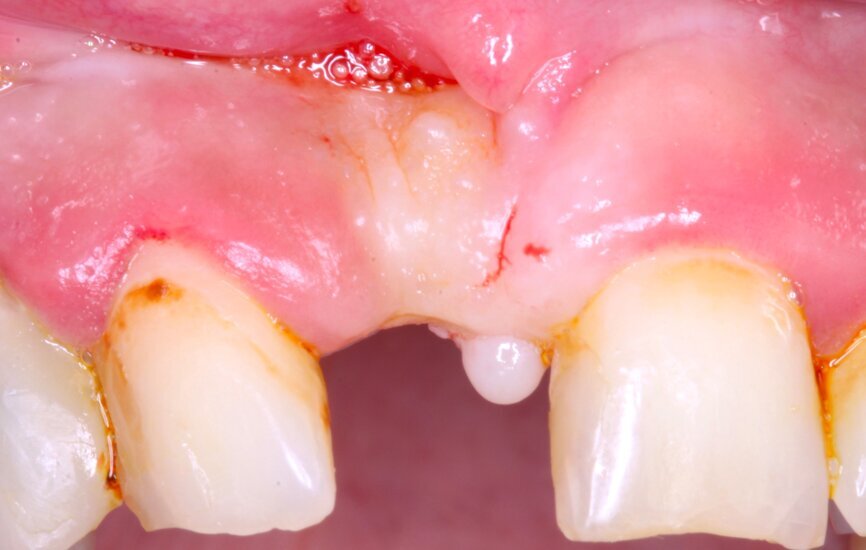

Fig. 1

Figura 1

1. Anestesia infiltrativa vestibular y lingual o palatina en la zona a intervenir.

2. Incisión paracrestal 2 mm hacia el palatino con hoja de bisturí 15C e intrasurcular al diente adyacente. Realización de la descarga de la distadora para una correcta visión del campo quirúrgico.